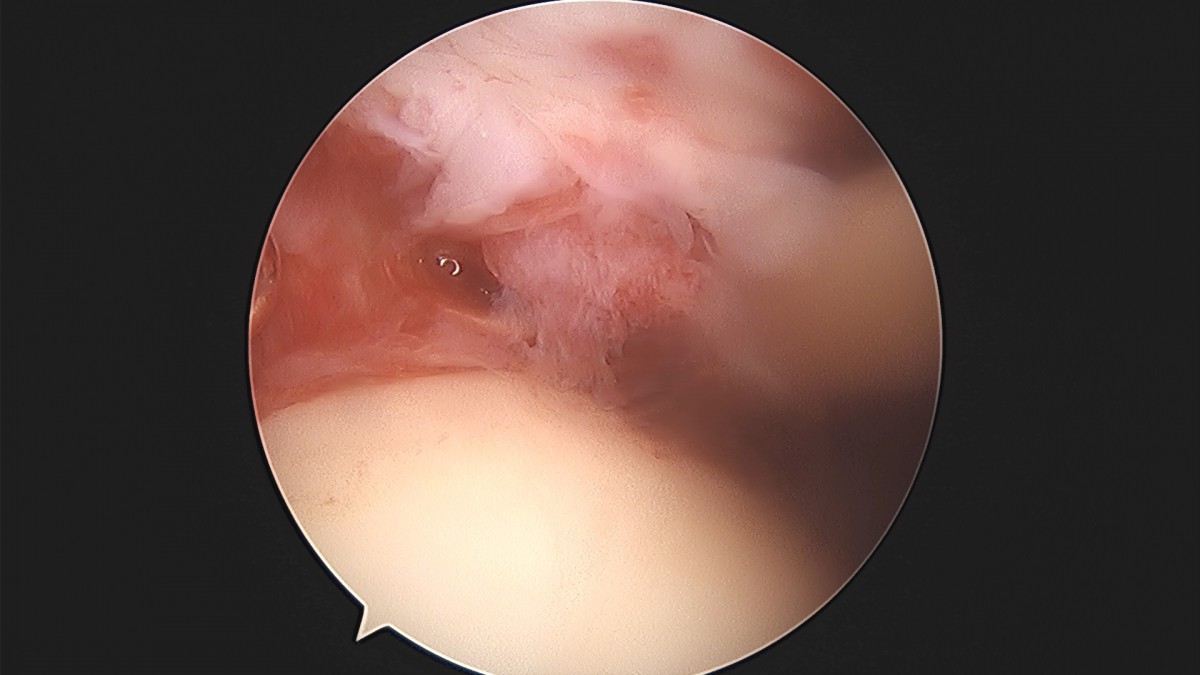

이재상원장님 어깨 견봉하 감압술 및 관절낭 이완술 박창O 환자

dae765e4d9ac96aee867c9d6292d8784_1758004611_0512.jpg